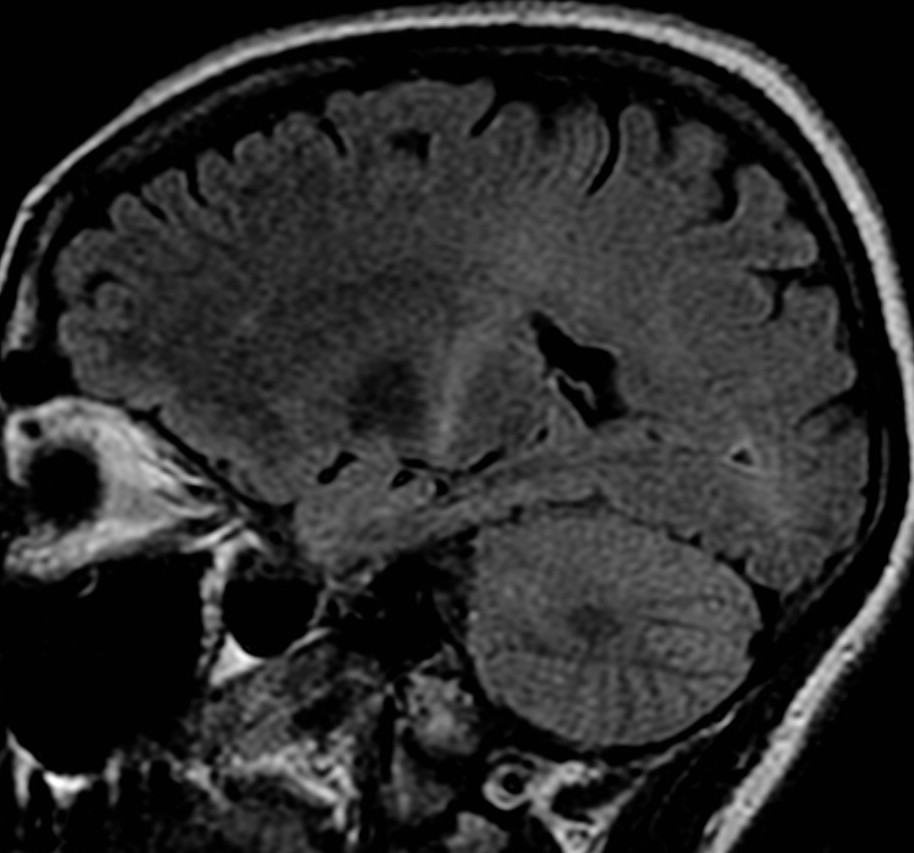

Sagittal MRI scan of the brain showing detailed structures including the cerebral cortex, cerebellum, and brainstem. The image highlights the gray and white matter differentiation and the ventricular system.

MRI of a brain potentially at risk for ALS (Wikimedia Commons)